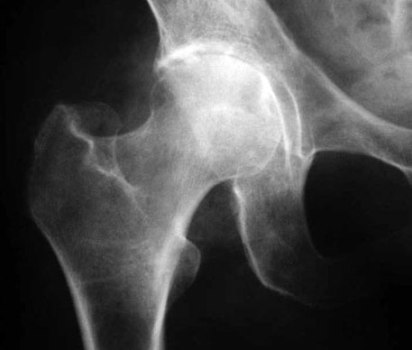

В рентгенологический кабинет клиники №1 ВиТерра Беляево к врачу-рентгенологу обратилась пациентка О., 64 года, с жалобами на сильные боли в тазобедренном суставе - при ходьбе и в покое, так же после интенсивной физической нагрузки появляется хромота. Пациентке была выполнена рентгенография тазобедренного сустава, в прямой проекции.

На рентгенологическом снимке тазобедренного сустава, в прямой проекции, визуализируется значительное неравномерное сужение суставной щели (более, чем наполовину от нормальной высоты). Уплотнены, неравномерно утолщены замыкательные пластины смежных суставных поверхностей, субхондральный остеосклероз. Головка бедренной кости несколько смещается кверху, деформируется и увеличивается в размере, контуры чёткие и ровные. Умеренно выраженные костные разрастания по краям головки и вертлужной впадины. Уплотнение хрящевой губы. Метапластическое обызвествление в местах прикрепления связок, сухожилий.

Заключение: Рентгенологическая картина коксартроза 2ст.